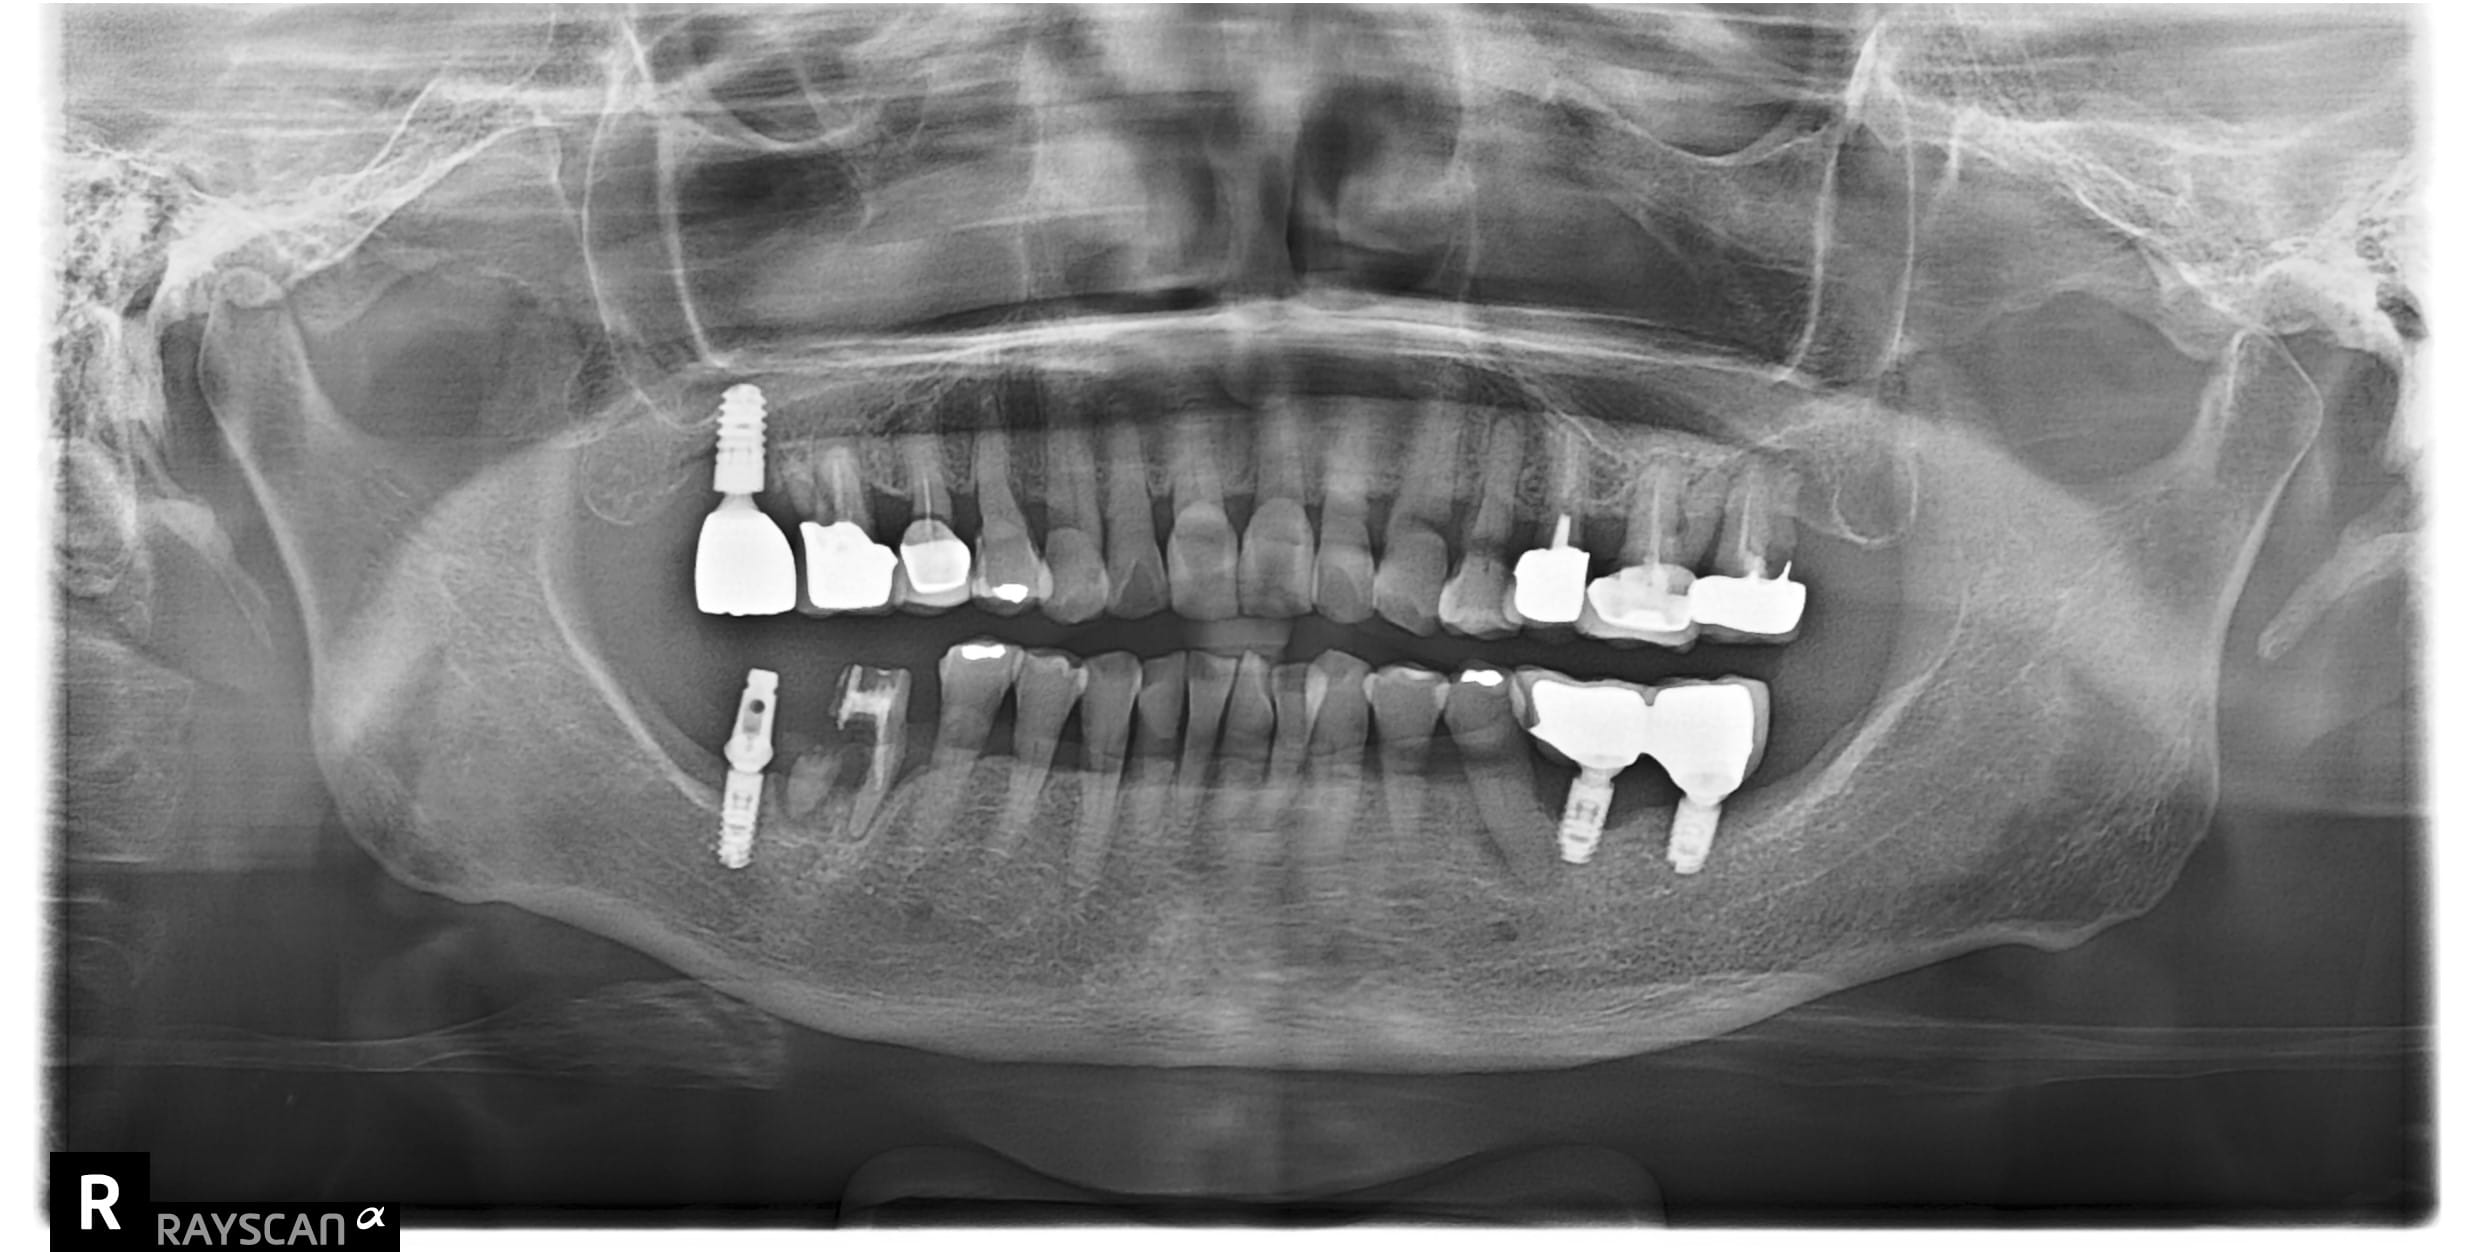

c先生因左上第一大臼齒根管後未裝牙套吃東西咬裂,故尋求協助治療。 牙齒裂致根部,需先拔除待傷口1-2

自述#46缺牙十年左右 想植牙改善右下第二大臼齒往前倒的狀況 骨頭狀況良好可直接植牙,等植牙接出後需

左下第一二大臼齒有膿包周囊袋過深,發現牙根斷裂 即拔即種當下清除發炎組織再補骨促進骨整合 左半邊咬合

左上第一小臼齒蛀牙缺損 齒質蛀牙嚴重導致斷裂,骨頭破壞需植入牙根時補骨促進骨整合 待3個月後骨整合完

右下第一大臼齒蛀斷 原右下第一.二大臼齒假牙相連,因右下第一大臼齒蛀牙到根部,導致兩顆假牙脫落,右下